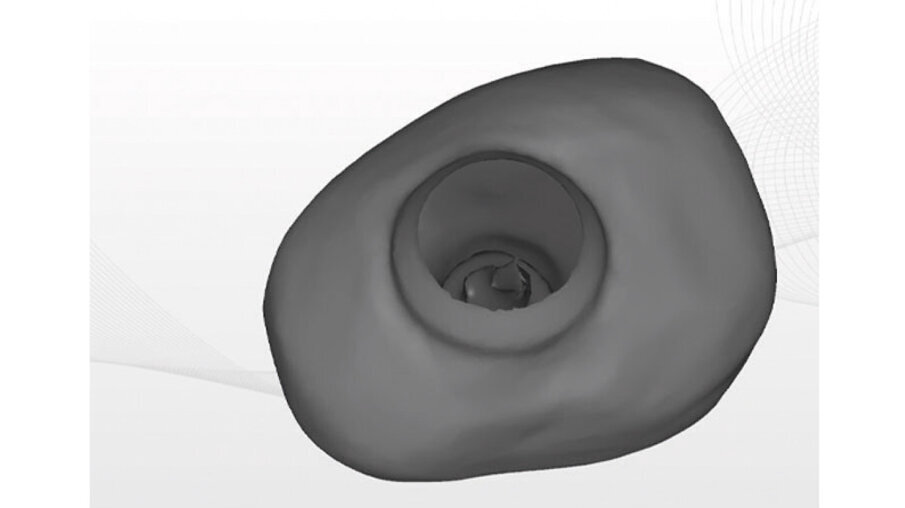

La vite di guarigione è stata costruita con tecnica CAM mediante fresatore 5X a partire da un blocchetto riempito di Polimetilmetacrilato (PMMA), con residuo di monomero inferiore allo 0,02%. La progettazione CAD è stata fatta con apposito software exocad (Figg. 8a-8c). L’impronta pre-operatoria e intra-operatoria sono state confrontate per ottenere il progetto della vite. L’impronta pre-operatoria del dente da estrarre è stata utilizzata come base per la forma del provvisorio. L’unica modifica apportata è stata quella di abbassare il piano occlusale in modo che la vite non interferisse con i carichi. L’impronta intra-operatoria invece è stata usata per ottenere la corretta posizione dell’impianto.

Figg. 8a-8c - Progettazione CAD della vite di guarigione customizzata.